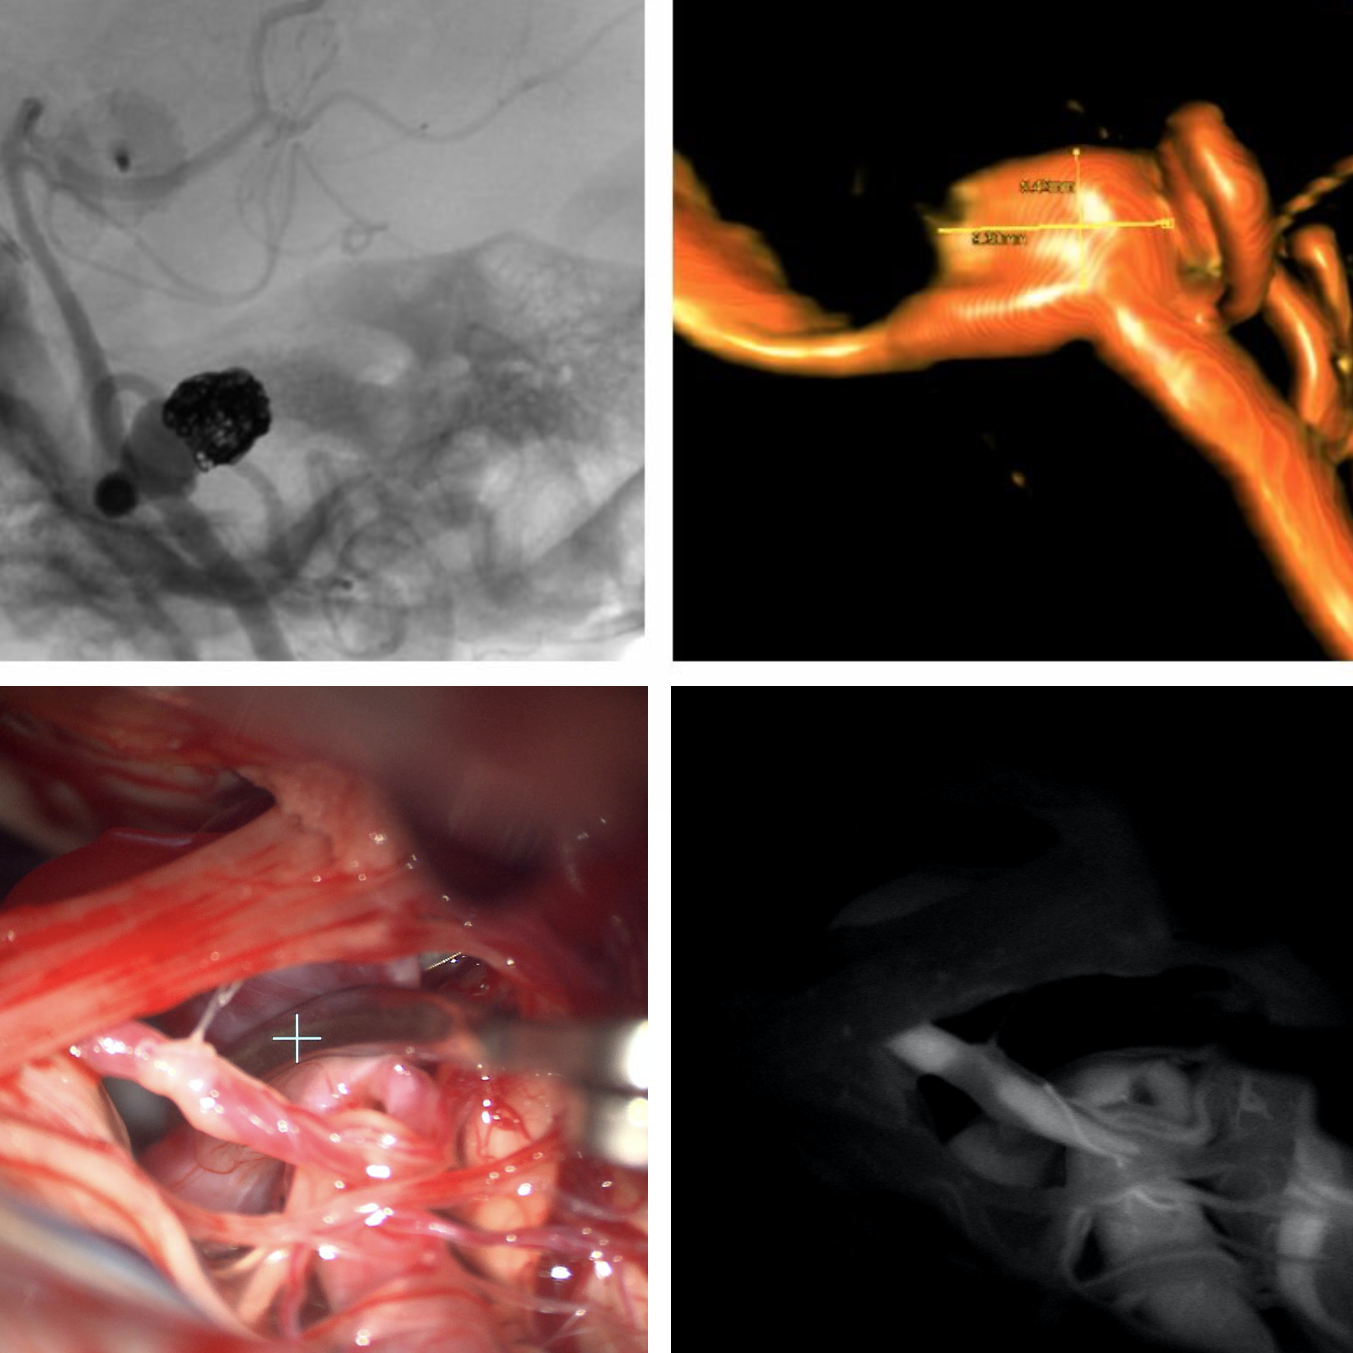

Die Mikrochirurgische Klippung zerebraler Aneurysmen ist durch die Anwendung moderner intraoperativer bildgebender Verfahren (vor und nach Aneurysmaverschluss) wie z.B. die Intraoperative Angiographie, Indocyaningrün (ICG) Videoangiographie und 3D-Endoskopie, sowie Fortschritte in der präoperativen Diagnostik und in der Intensivmedizin weiter optimiert worden. Jede offene, elektive Gefäß-Operation wird mittels intraoperativem Neuromonitoring überwacht, um die Sicherheit des Eingriffs zu erhöhen. Diese medizinisch-technischen Fortschritte haben wesentlich dazu beigetragen, die mikrochirurgische Behandlung zerebraler Aneurysmen heutzutage sicher und relativ gefahrlos zu gestalten.

Die endovaskuläre Therapie zerebraler Aneurysmen wird seit 1983 an der Univ.Klinik für Neurochirurgie Wien durchgeführt. Der Zugang zum Aneurysma erfolgt nicht über eine chirurgische Schädelöffnung, sondern von „innen“ über das Gefäßsystem. Dazu wird die Leistenarterie punktiert und ein weiches Kunststoffröhrchen, ein sog. Katheter, unter Röntgendurchleuchtung bis in die hirnversorgenden Halsschlagadern hochgeführt. Aus dieser Position werden Gefäßfüllungen, sog. Angiographien, durchgeführt.

Die Angiographie ist eine Untersuchungsmethode, bei welcher unter Röntgendurchleuchtung ein Kontrastmittel durch einen Katheter in die hirnversorgenden Gefäße injiziert wird, wodurch gesunde und krankhaft veränderte Hirngefäße dargestellt werden können. Durch diesen Katheter wird ein dünnerer Katheter, der sog. Mikrokatheter, bis in das Aneurysma hochgeführt. Der Mikrokatheter transportiert Platinspiralen (Coils), welche im Aneurysma abgesetzt werden und die Blutgerinnung stimulieren. Durch Bildung eines Blutgerinnsels und spätere Vernarbung kommt es zu einem „biologischen“ Verschluss des Aneurysmas, wodurch zukünftige Aneurysmablutungen verhindert werden können.

Für die Behandlung sehr großer, sog. komplexer Aneurysmen stehen zusätzlich weitere Techniken zur Verfügung: In diesen schwierigen Fällen ist ein sicherer Aneurysmaverschluss oftmals nur durch Verschluss des Trägergefäßes unter Bypassschutz möglich.

Wenn also der Aneurysmaverschluss weder chirurgisch noch endovaskulär unter Erhalt des aneurysmatragenden Gefäßes möglich ist, kann das Aneurysma gemeinsam mit jenem Hirngefäß, aus welchem es sich entwickelt hat, verschlossen werden.

Vor diesem sog. „therapeutischen“ Gefäßverschluss müssen zahlreiche Maßnahmen getroffen werden, um Schlaganfälle und andere schwerwiegende neurologische Konsequenzen zu vermeiden. Deshalb wird vor dem therapeutischen Gefäßverschluss ein Bypass angelegt, um das Hirngewebe nach dem Gefäßverschluss ausreichend mit Blut zu versorgen.